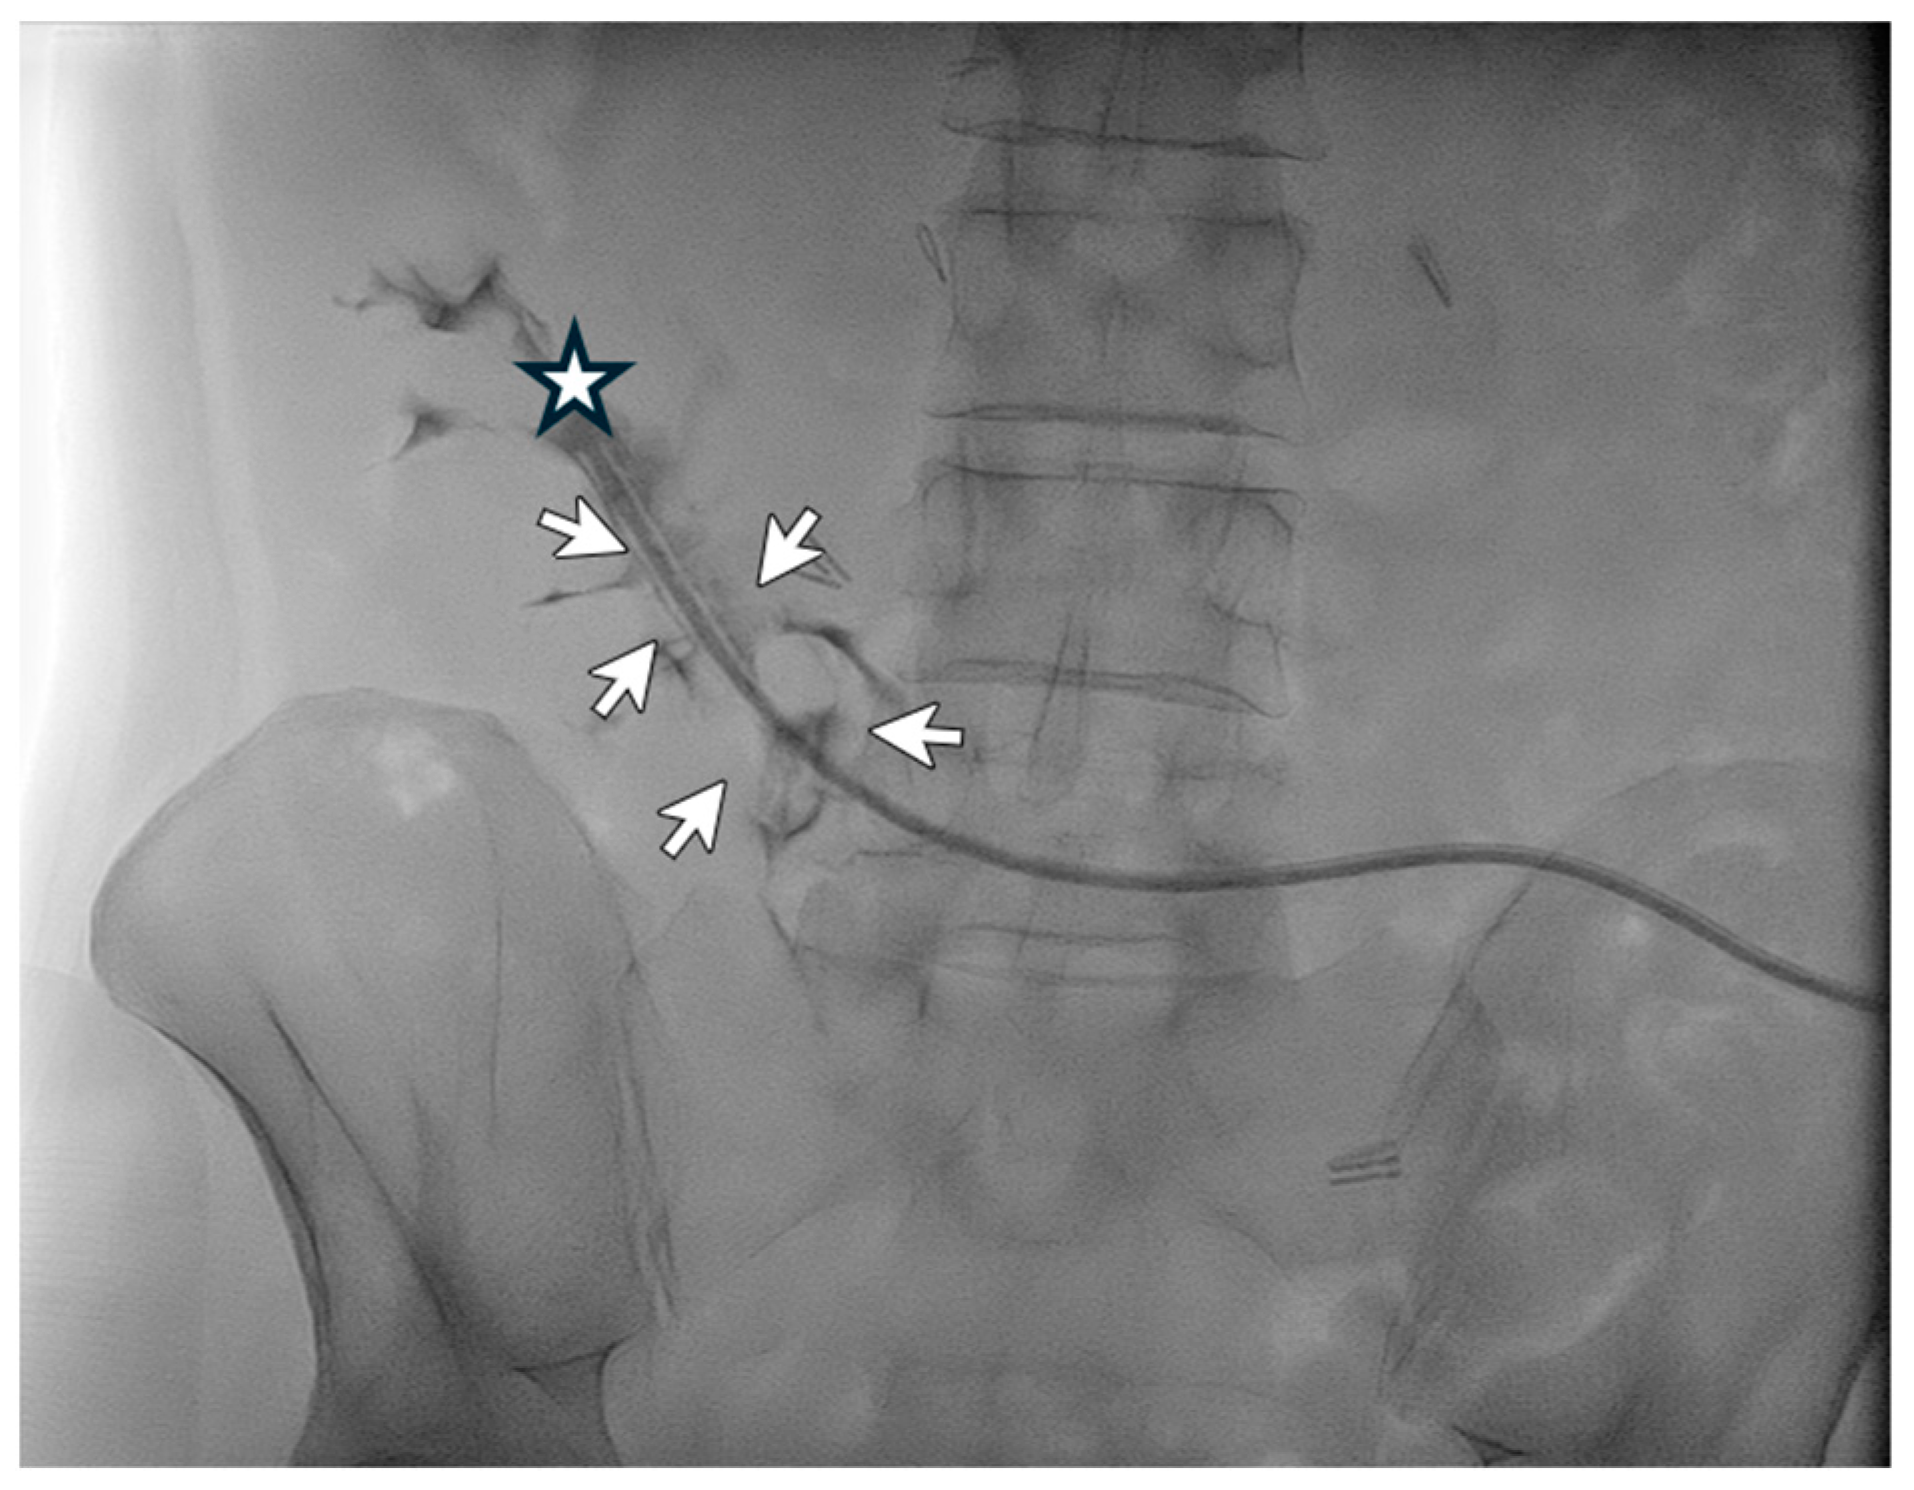

A 48-year-old male patient affected by ADPKD underwent right nephrectomy and concurrently videolaparoscopic peritoneal catheter placement. Two months later, due to persistent abdominal bulk secondary to the contralateral kidney size, the patient underwent a second surgery for left nephrectomy. Three months after the start of peritoneal dialysis, poor inflow and outflow performance was detected with little benefit from laxatives administration. An abdomen X-ray showed the peritoneal catheter rising from the lumbar left region with the tip ending in the lumbar right region (Figure 1).

The next day—after adequate antibiotic prophylaxis—the patient underwent catheterography and radiological manipulation of the catheter with repositioning of the catheter tip in the pelvis. Afterward, the patient could immediately and effectively resume peritoneal dialysis, and no complication of the procedure occurred. The peritoneal catheter was well-functioning one month after the procedure.

Figure 1. Catheterography showing the tip (Life 14 01475 i001) of the peritoneal catheter pointing to the lumbar right region. Normal spillage of the contrast medium from the side holes may be seen (Life 14 01475 i002).